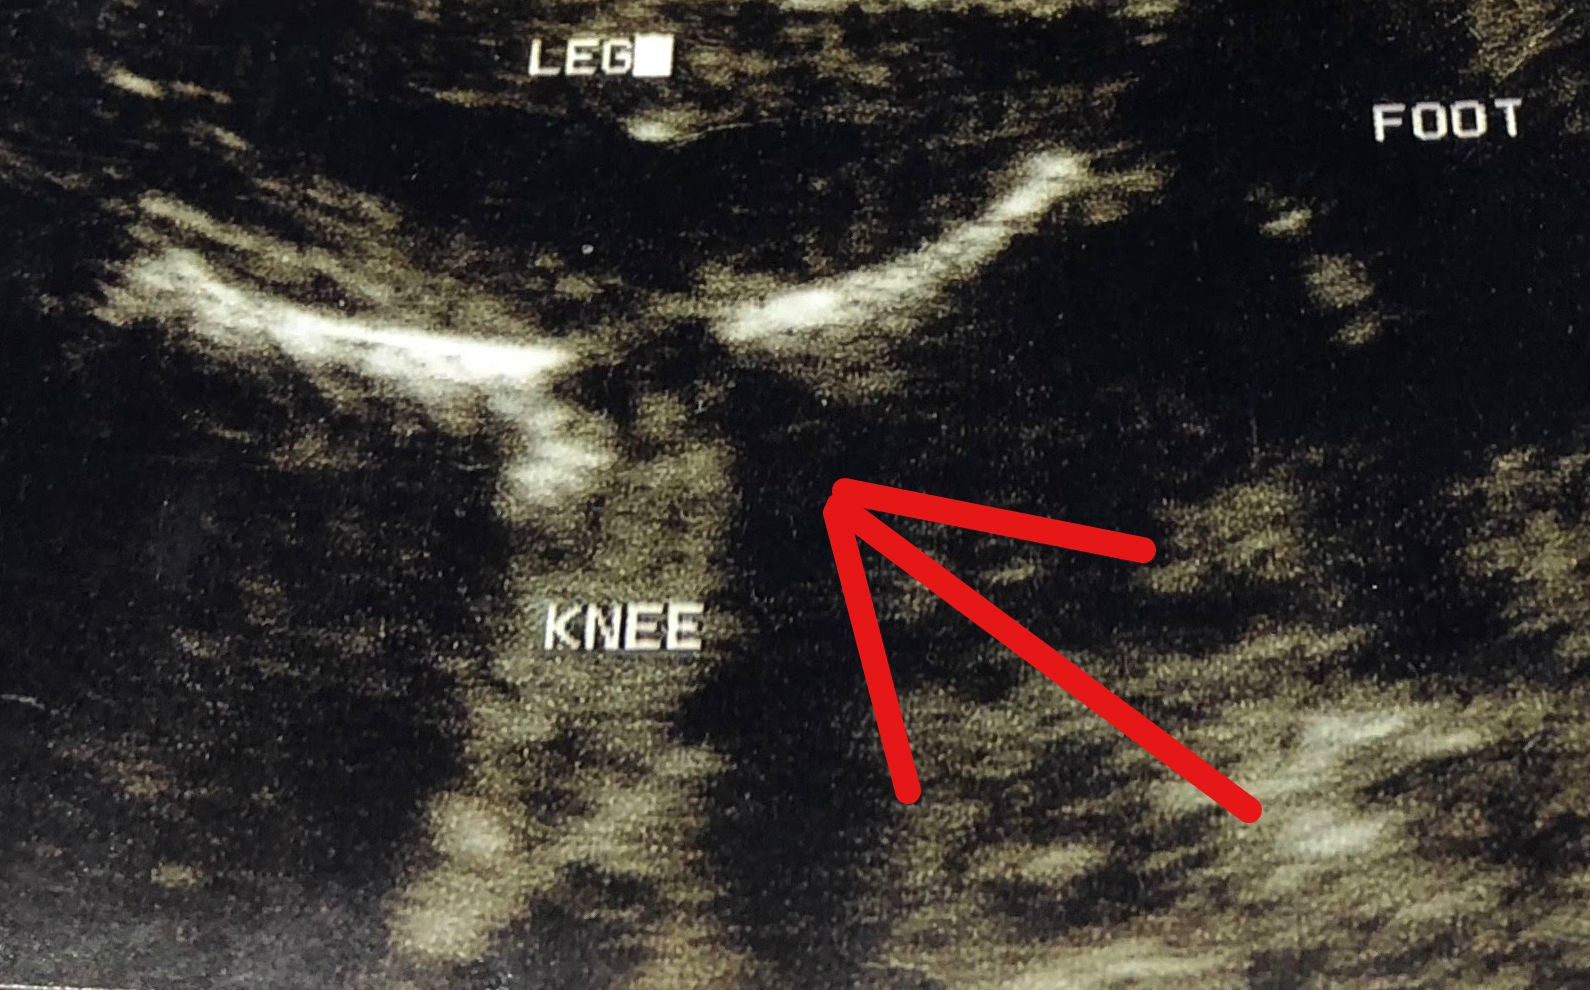

Here’s a close-up of the image: